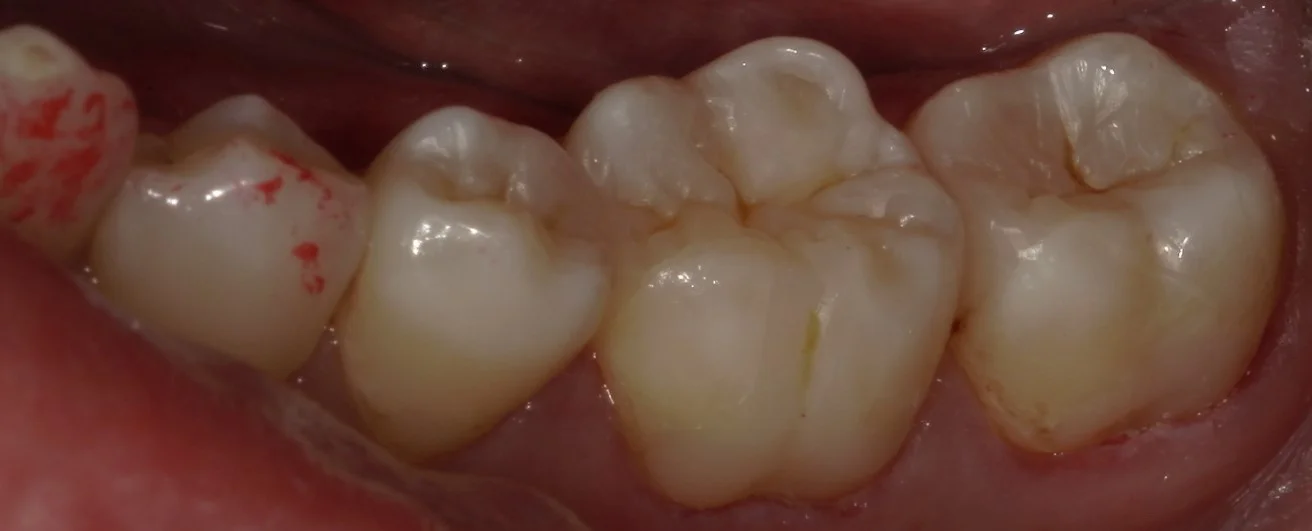

虫歯を取りきったのがこちらの写真です。

ところどころ黒い部分が残っているように見えますが、この部位は着色が付いているだけで、虫歯になっている所ではありません。

ここを完全に取りきろうとすると、神経にダメージが行ってしまう可能性が高かったため、今回は除去しないで温存しておくこととしました。

通常、これほどのサイズの虫歯であれば・・・

左から順に

金属の詰め物・金属の被せ物・金属の被せ物

という治療方針になることが多いかと思われます。

ダイレクトボンディングであれば、残っている部分の歯質をそのまま温存して治療を終了させることが出来る為、被せ物や詰め物と違って歯を無駄に大きく削る必要がありません。